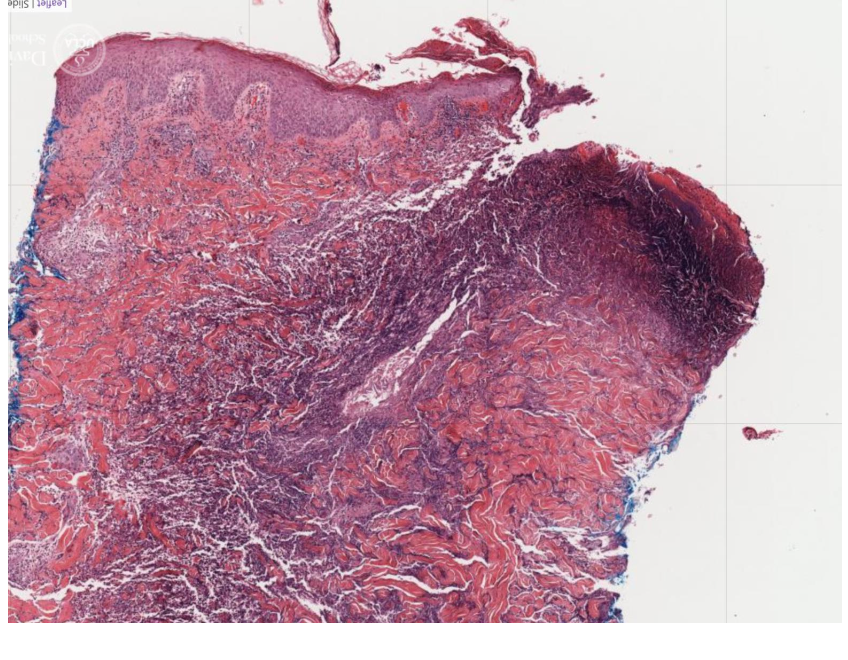

name the biological process shown in this image

chronic inflammation

lymphocytes